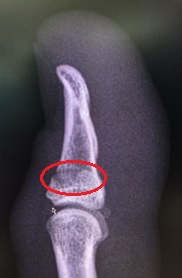

My Ironman (IM) trg has taken a bit of a hit. In a build-up half IM race I decided to trow myself off my bike but not forgetting to do my best superman impression before hitting the deck pretty hard. My initial annoyance was the damage to my bike; carbon fibre is costly! Although pretty battered, bruised and scratched (mainly to my pride), in good old Army fashion, I soldiered on finishing the remaining 20km of the bike leg and the 21km run. Post-race clean-up and a trip to A&E the next day confirmed I had actually broken my thumb; I did feel a fair amount of pain whilst trying to change gear – now I know why.

What impressed me most during my treatment was the thermoplastic thumb splint (available in a choice of colours) complete with water friendly Velcro securing strap, although I’ve already got some design mods in mind for version two. It means I can still compete in my next half IM trg race in 2 weeks’ time before the thumb is estimated to be fully healed 6 weeks from now.

Below are some pics…